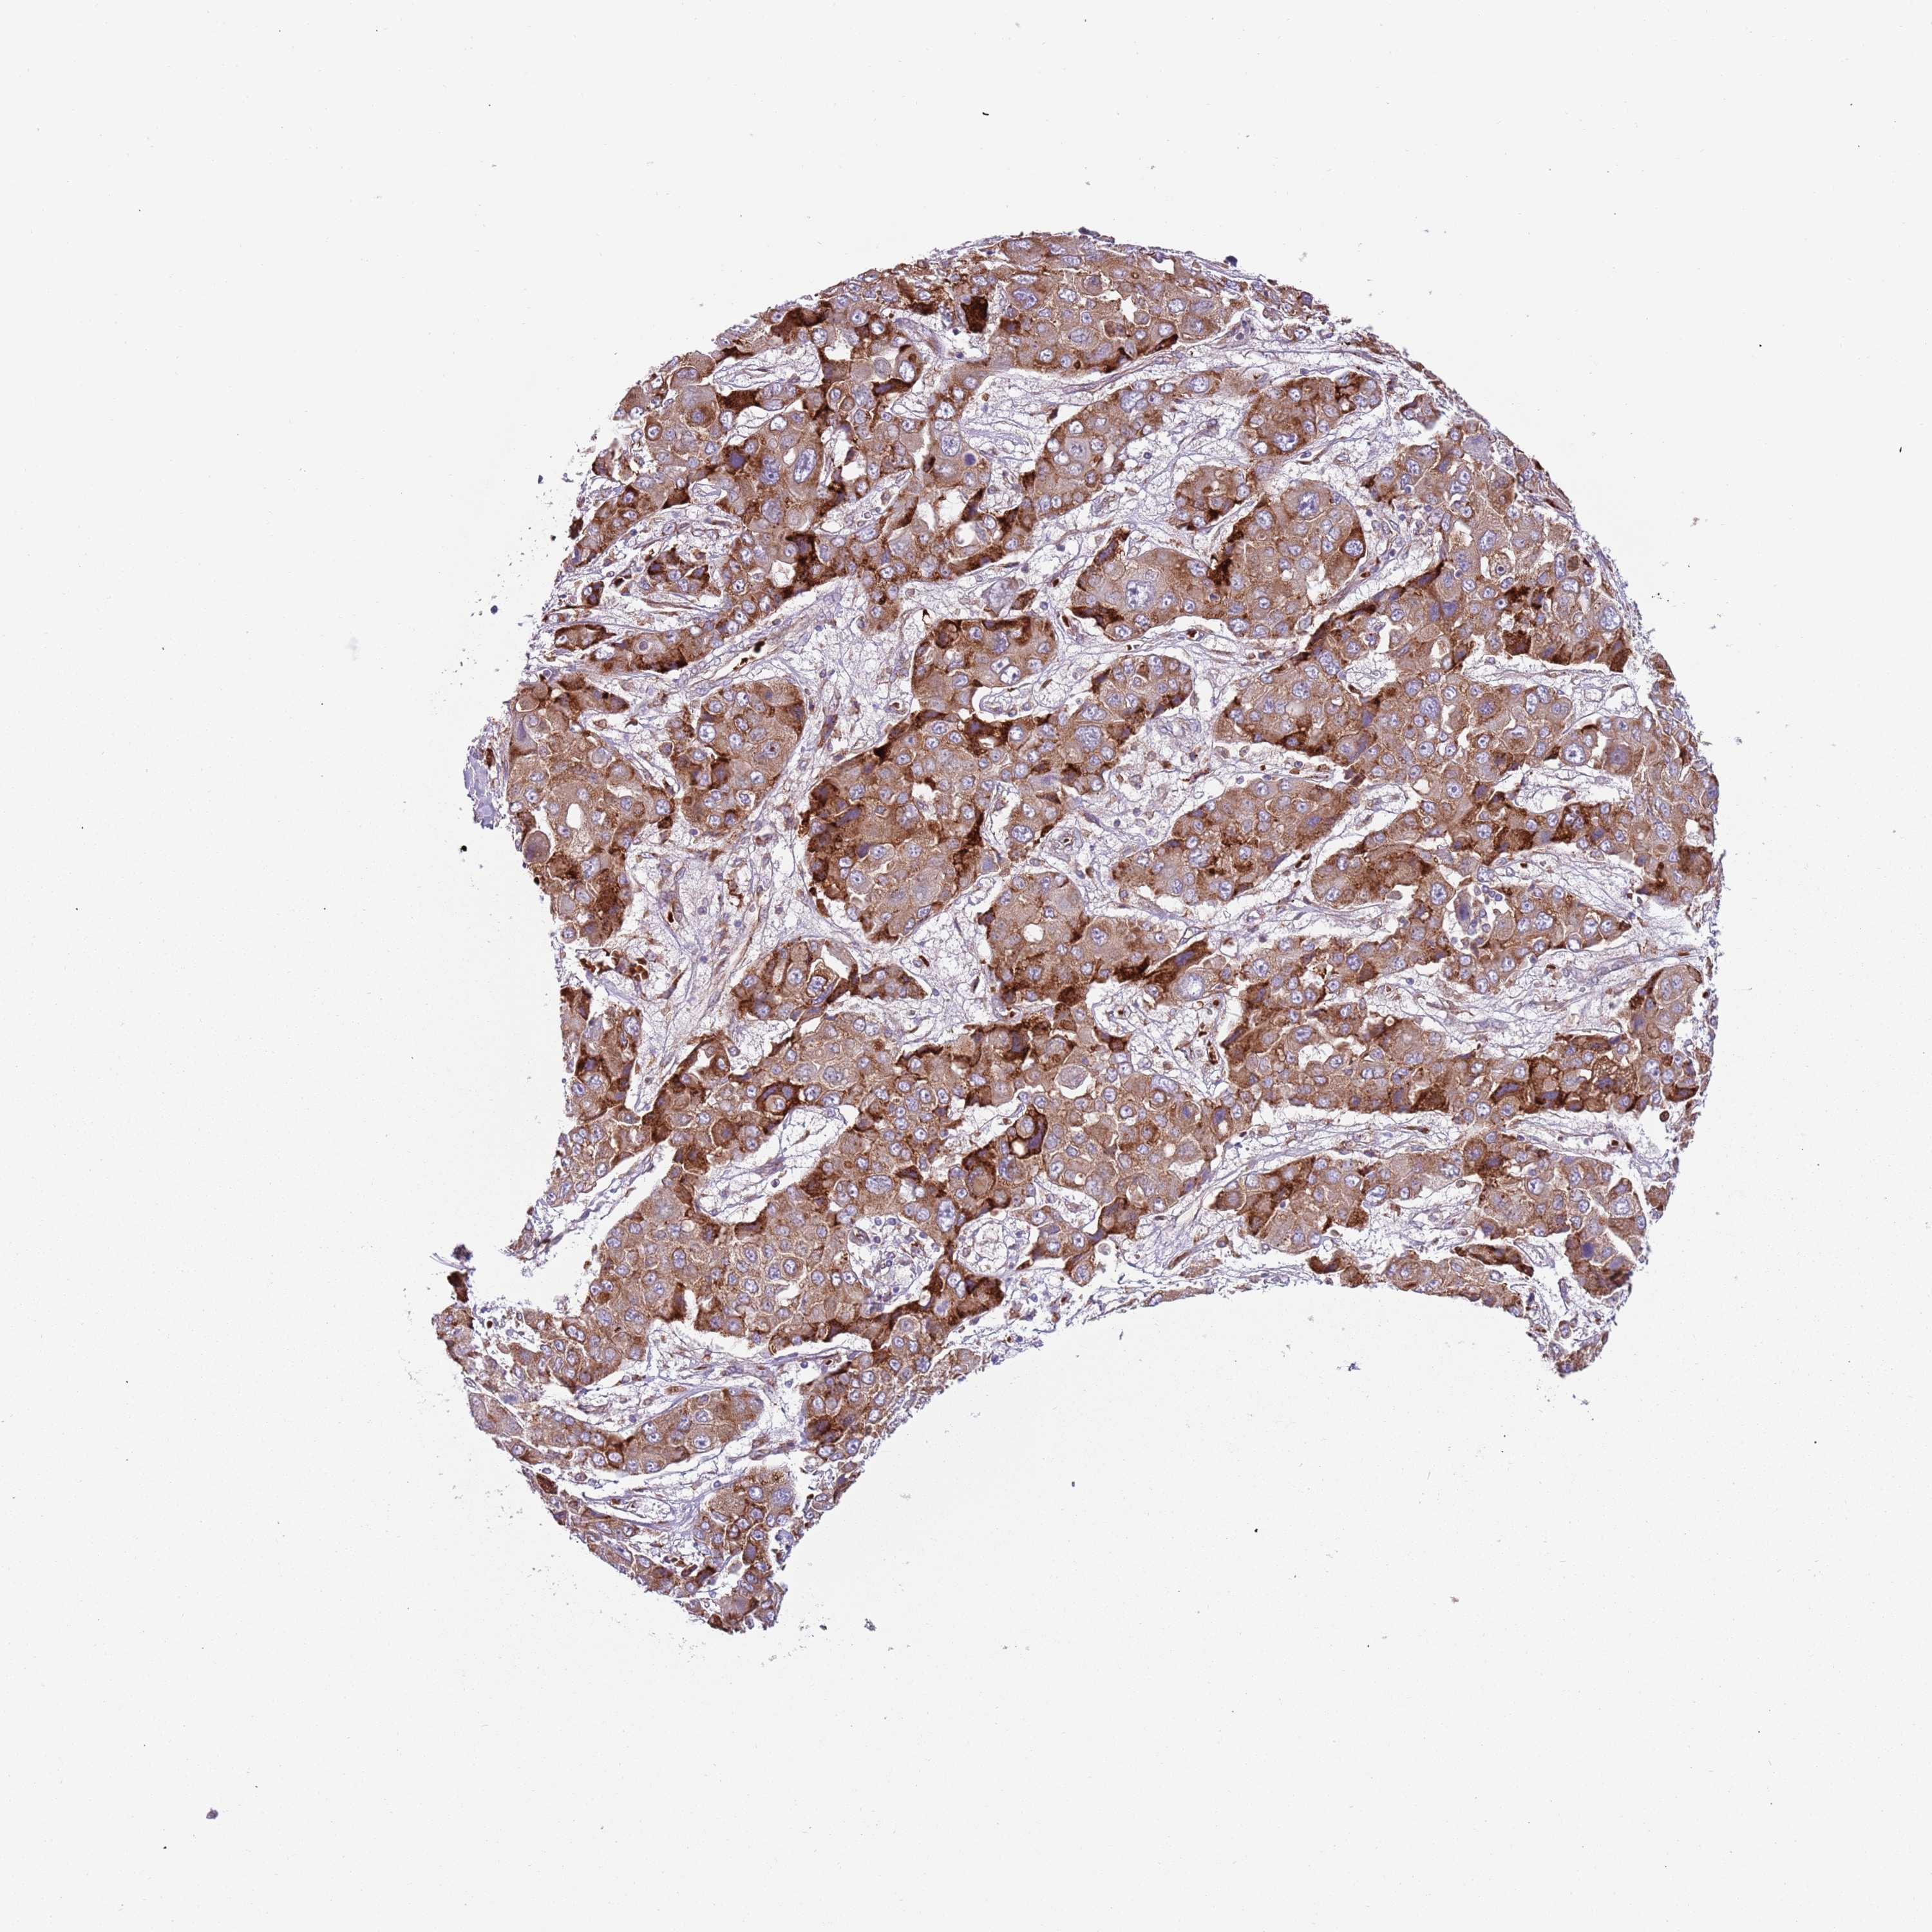

LIVER CANCER - Protein expressioni

A mouse-over function shows sample information and annotation data. Click on an image to view it in a full screen mode. Samples can be filtered based on level of antibody staining by selecting one or several of the following categories: high, medium, low and not detected. The assay and annotation is described here.

Note that samples used for immunohistochemistry by the Human Protein Atlas do not correspond to samples in the TCGA dataset.

Antibody stainingi

Antibody staining in the annotated cell types in the current human tissue is reported as not detected, low, medium, or high, based on conventional immunohistochemistry profiling in selected tissues. This score is based on the combination of the staining intensity and fraction of stained cells.

Each image is clickable and will lead to virtual microscopy that enables deeper exploration of all samples and also displays staining intensity scores, fraction scores and subcellular localization as well as patient and tissue information for each sample.

Antibody HPA040401

Antibody HPA043921

Staining

High

Medium

Low

Not detected

Intensity

Strong

Moderate

Weak

Negative

Quantity

>75%

75%-25%

<25%

None

Location

Nuclear

Cytoplasmic/membranous

Cytoplasmic/membranous,nuclear

Cholangiocarcinoma

Carcinoma, Hepatocellular, NOS